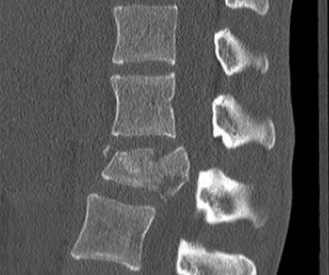

CASE 1 A 63-year-old male sustained a hyperextension injury to his neck while diving into a pool. Upon presentation, he reports decreased sensation in his hands and decreased strength in his arms and wrists, but no lower extremity complaints. On motor examination, he has 5/5 strength in his deltoids and elbow flexors and 4/5 strength in the elbow extensors, wrist extensors, and finger flexors. Lower extremity motor examination is normal. Sensation is decreased to light touch in both hands. Otherwise his sensation is preserved. Images of his cervical spine are shown in Figures 1–1 to 1–3.

Figure 1–1

The correct answer is (B). The clinical scenario describes a patient with central cord syndrome (CCS). CCS continues to be the most common incomplete spinal cord injury accounting for 15.7% to 25% of all spinal cord injuries. The characteristic presentation is an extension moment injury in a previously spondylotic and stenotic spine. Figures 1–1 to 1–3 demonstrate a spondylotic spine with central narrowing and CSF effacement that is worst at the C3–4 level. Bleeding, edema, and/or Wallerian degeneration lead to damage of the lateral corticospinal tract which is the main descending motor tract in the spinal cord. The more central anatomic position of the homunculus to the upper extremities places them at greater risk than those to the lower extremities. As such, injury to the lateral corticospinal tract is characterized by upper more than lower extremity involvement and motor deficits being more pronounced than sensory deficits.